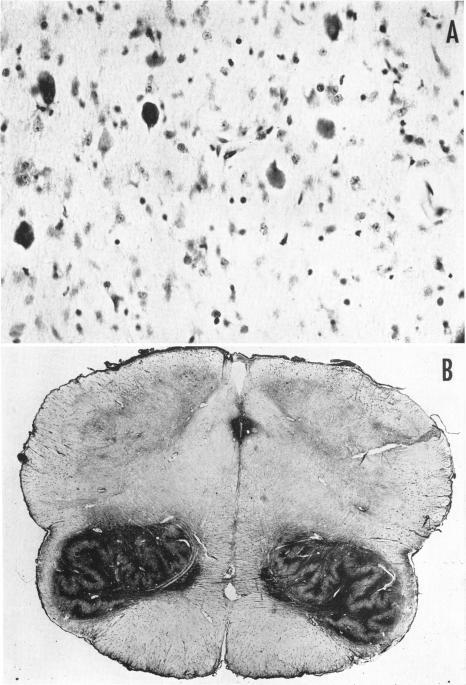

RICHTER R B

Am J Hum Genet. 1950 Mar;2(1):1-29.